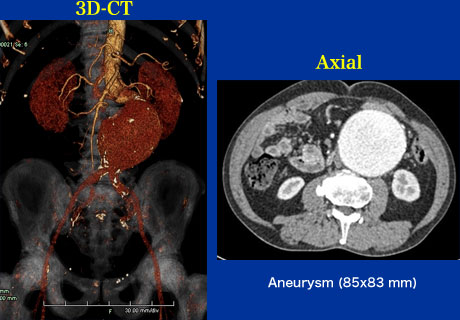

症例17

検査異常

【起始・経過】

2006年肺癌治療中に5cmの腹部大動脈瘤を指摘された。手術リスクが高いため経過観察されていたが、5.5cmまで増大したためステントグラフト術目的で当院紹介となった。

【既往歴】

77歳 肺癌(動注化学療法施行中)

高血圧(+) 糖尿病(ー) 喫煙歴(+)

【治療計画】

Stent graft (Zenith)

症例17 CTA